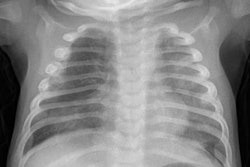

VIENNA - The "half-slice thickness" approach is a practical and cost-effective way to reduce CT dose, particularly for children, and it doesn't require additional hardware or staff. That’s the view of Dr. Erich Sorantin, professor and acting head of the division of pediatric radiology at Medical University of Graz in Austria. In an interview with AuntMinnieEurope.com Editor-in-Chief Philip Ward at ECR 2016, he elaborates on how the technique works.